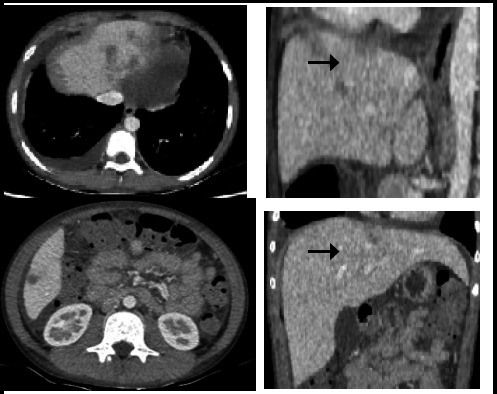

伴有呼吸窘迫和多器官受累的高嗜酸性粒细胞综合征在儿童中并不常见。必须根据临床、实验室和影像学特征来识别这种病症。应尽早使用皮质类固醇,以稳定患者病情并防止器官受损。热带感染是儿童常见的继发性病因,因此需要服用地西泮。我们介绍了一例呼吸窘迫、嗜酸性粒细胞明显增多、器官涉及肺部(肺部浸润伴积液)、心脏(心包积液)和腹部(腹水伴肝脏浸润)的青少年男性病例,该病例通过使用类固醇和抗蠕虫药得到了控制。该病例强调了识别嗜酸性粒细胞过多综合征患者、进行全面评估和开始治疗的重要性。

Hypereosinophilic syndrome with respiratory distress and multiorgan involvement is not so common in children. It is essential to identify this entity based on clinical, laboratory, and imaging features. Corticosteroids should be instituted at the earliest to stabilize the patient and prevent organ damage. Tropical infections are a common secondary cause in children warranting the administration of Diethylcarbamazine. We present a case of an adolescent male in respiratory distress with marked eosinophilia and organs involving the lungs (pulmonary infiltrates with effusion), heart (pericardial effusion), and abdomen (ascites with infiltrates in the liver) which was managed with steroids and anthelmintics. The case highlights the importance of identifying patients with Hypereosinophilic syndrome in pursuing thorough evaluation and commencing therapy.